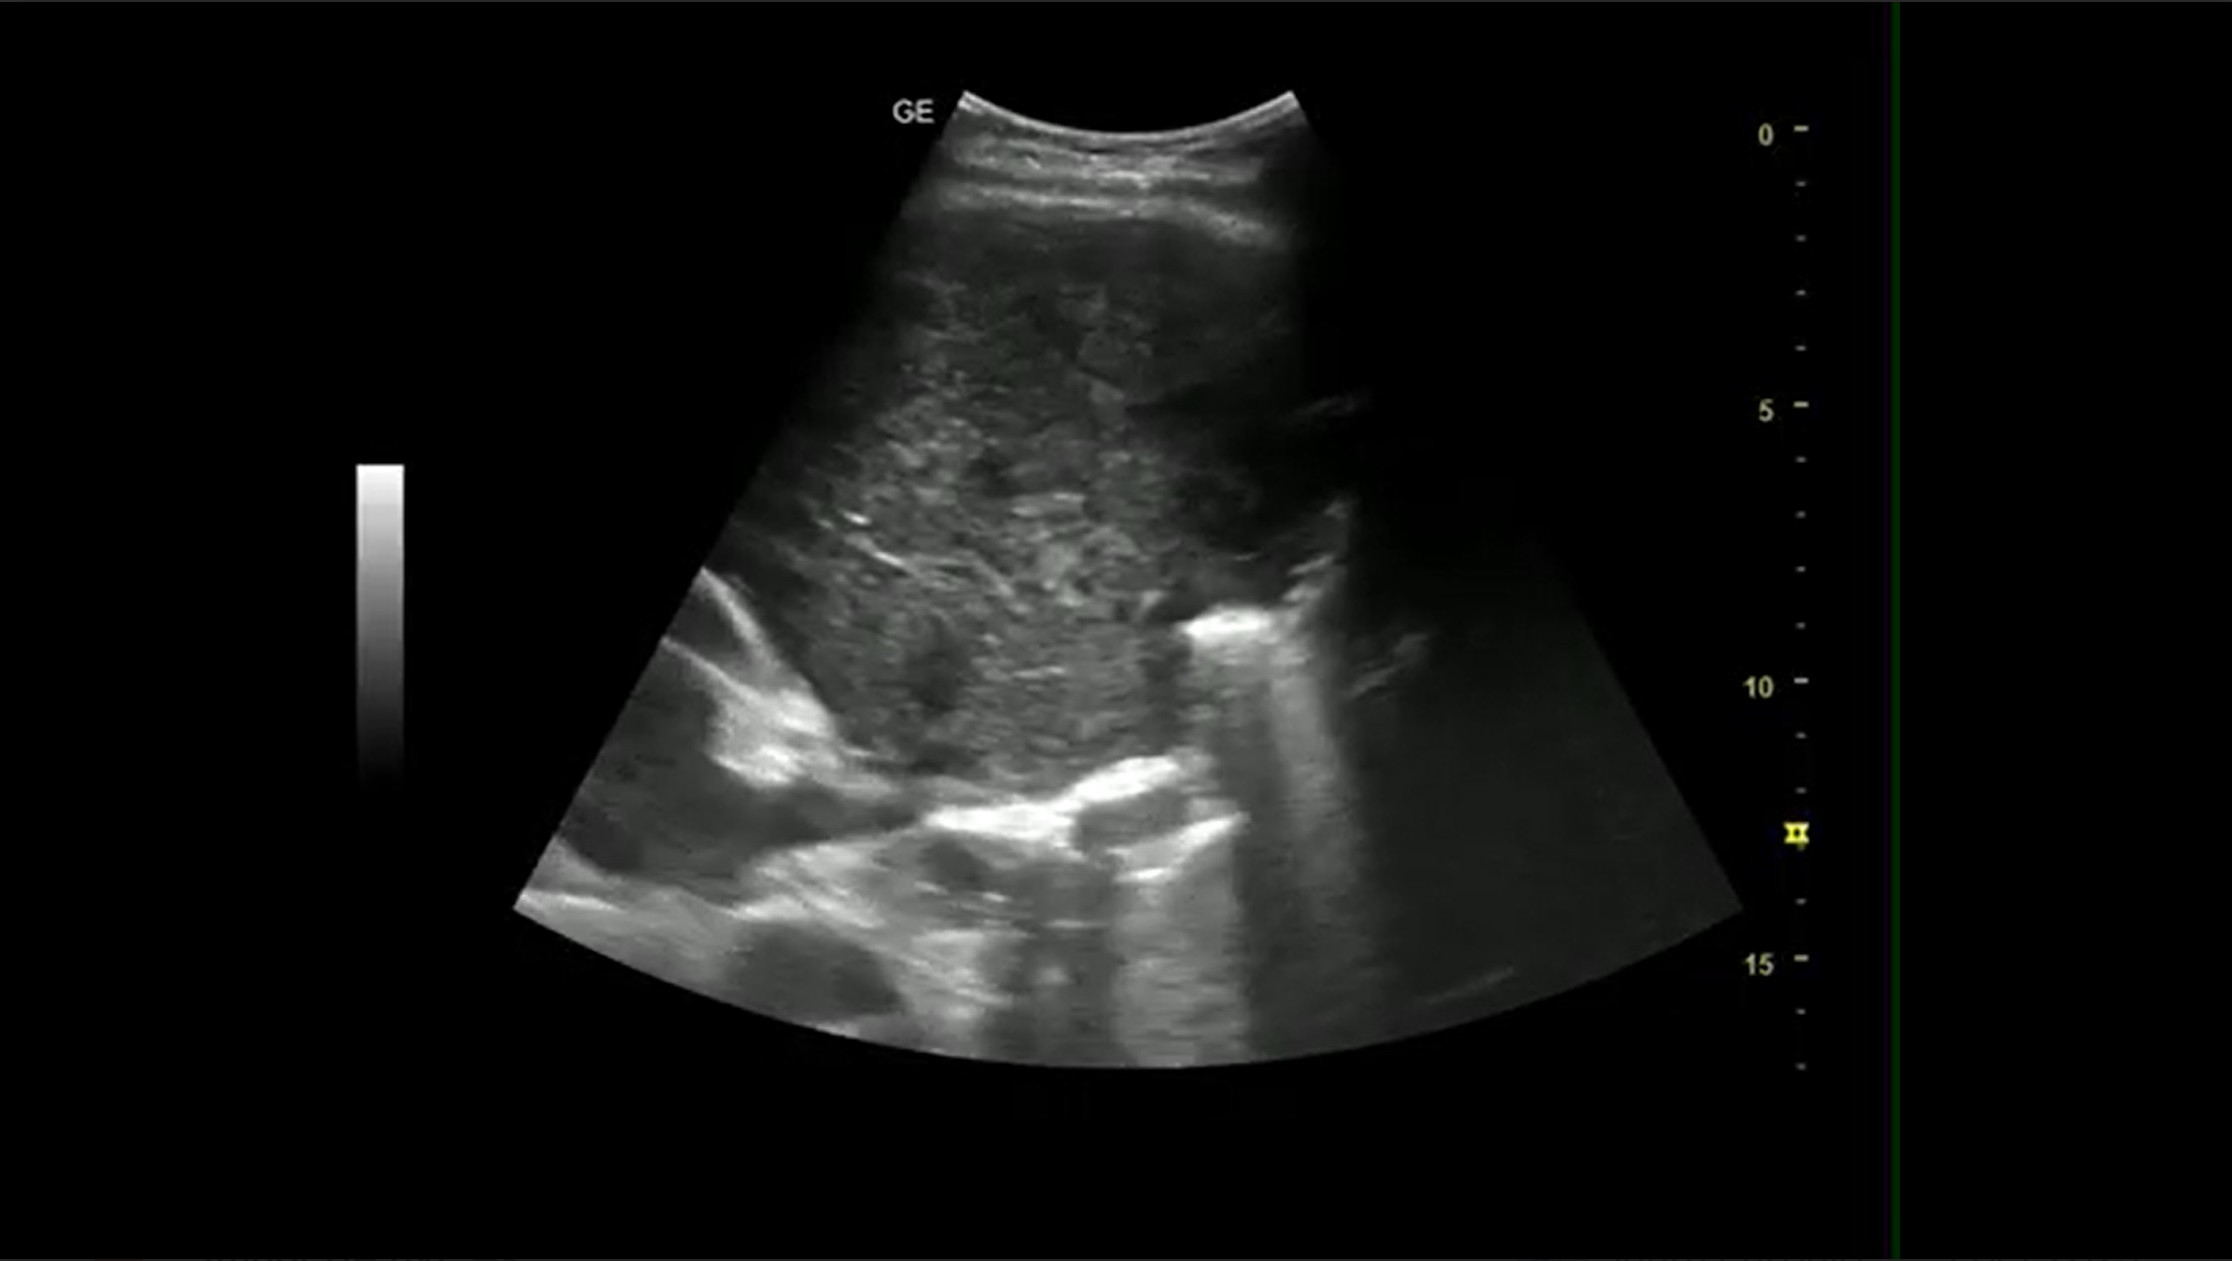

Las imágenes más relevantes observadas revelan los siguientes signos ecográficos:

1. Signo de la medusa: refleja el movimiento ondulante que presenta el pulmón consolidado por el derrame.

2. Hepatización pulmonar: la densidad ecográfica del pulmon se hace similar a la del hígado.